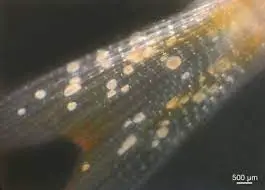

تروفونت انگل به شکل دونه های سفید کوچک در سطح بدن ماهی دیده میشه و ظاهری شبیه به گرد نمک ایجاد میکنن. تروفونت ها تو اپیتلیوم بافت های مخاطی ماهی مستقر میشن و از اونجا تغذیه میکنن و از 30 الی 40 میکرومتر تا 1000 میکرومتر در طی هفت روز در دمای 20 درجه سانتیگراد رشد میکنن.

اگرچه از روی ظاهر نقاط سفید در ماهیها میشه به بیماری “ایک” مشکوک شد، اما تائید قطعی این بیماری نیاز به شناسائی انگل در بافت آلوده ماهیان با استفاده از میکروسکوپ داره. برای اینکار لازمه از ماهیها لام مرطوب تهیه بشه. برای تهیه لام مرطوب از پوست بایستی با استفاده از یک لامل شیشه ای پهلوی ماهی رو از سر به طرف دم به آرامی خراشید به نوعی که تعدادی از سلول های پوستی (ترجیحا همراه با نقاط سفید) رو به همراه موکوس جمع آوری کنید و روی یه لام بذارید و زیر میکروسکوپ ببینین.

بعلاوه میتونین تیکه های خیلی کوچیک از لاملای آبشش و یا تیکه های کوچیک از دم و باله ها رو روی لام شیشه ای بذارین و بعد چند قطره آب روی اونها بریزین و یک لامل که سراسر نمونه را بپوشونه رو روی لام قرار بدین و اون رو با زیر میکروسکوپ بررسی کنین.

زیر میکروسکوپ باید تروفونت بالغ درشت، گرد یا بیضوی و به رنگ تیره است (بدلیل وجود مژه های ضخیمی که کل سلول را می پوشاند) که سایز آن به 5/0 تا 1 میلیمتر می رسه و یک هسته نعل اسبی داره رو ببینین. این مرحله از زندگی انگل اونقدر بزرگه که با بزرگنمایی 40 برابر هم به راحتی دیده میشه. در واقع این شکل از انگل مربوط به مرحله دوم زندگیشه. این مرحله از زندگی انگل یک حرکت چرخشی آرام و گاهی حرکت آمیبی داره و شما که با کمی تمرین میتونین به آسونی تشخیصش بدین.